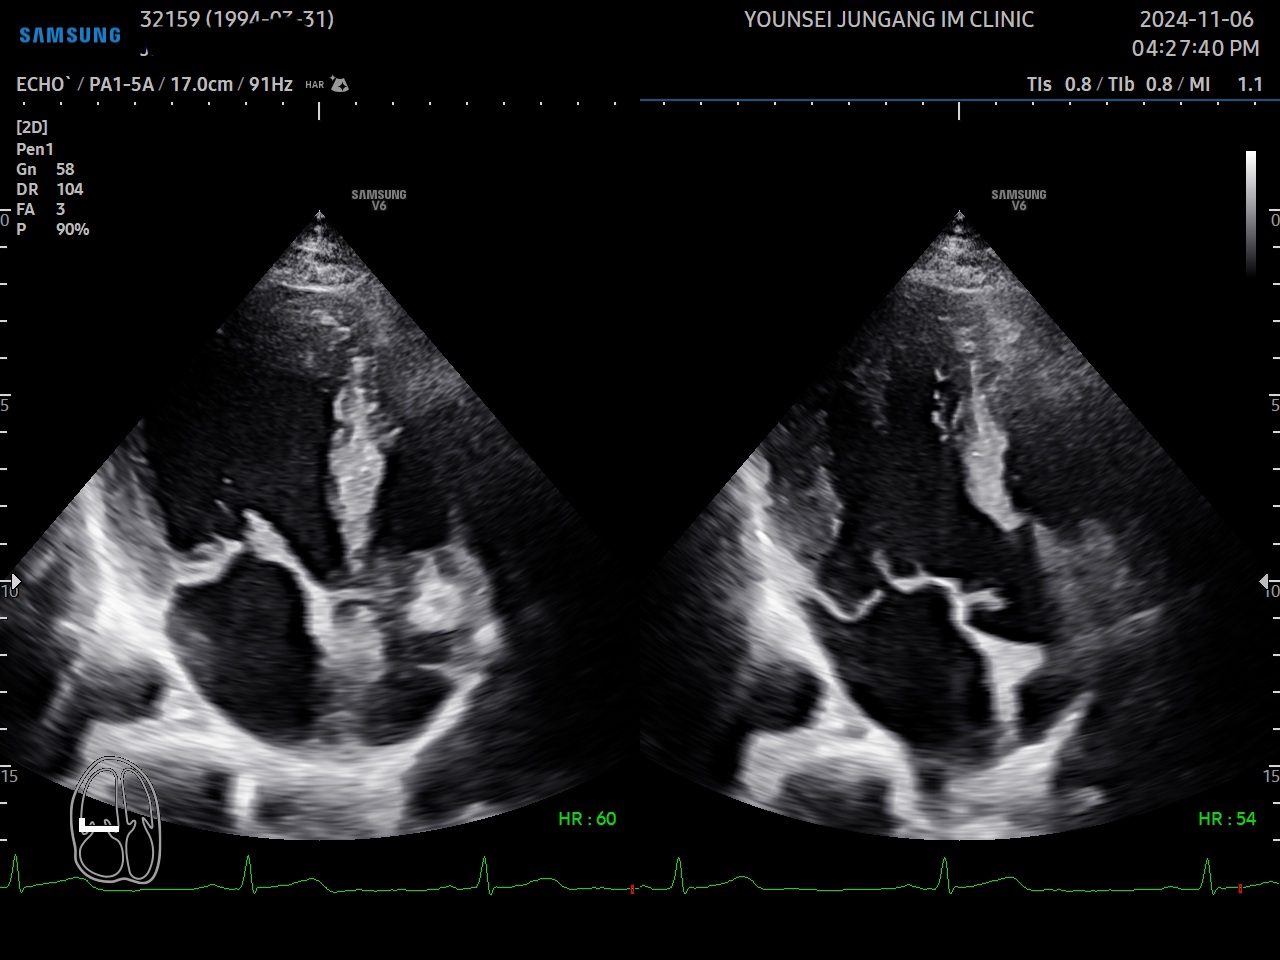

ÃÊÀ½ÆÄ°¶·¯¸®

ÀþÀº ³²¼º...

¿ì½É½Ç °æ...

ºñÈļº ½É...

È®À强 ½É...